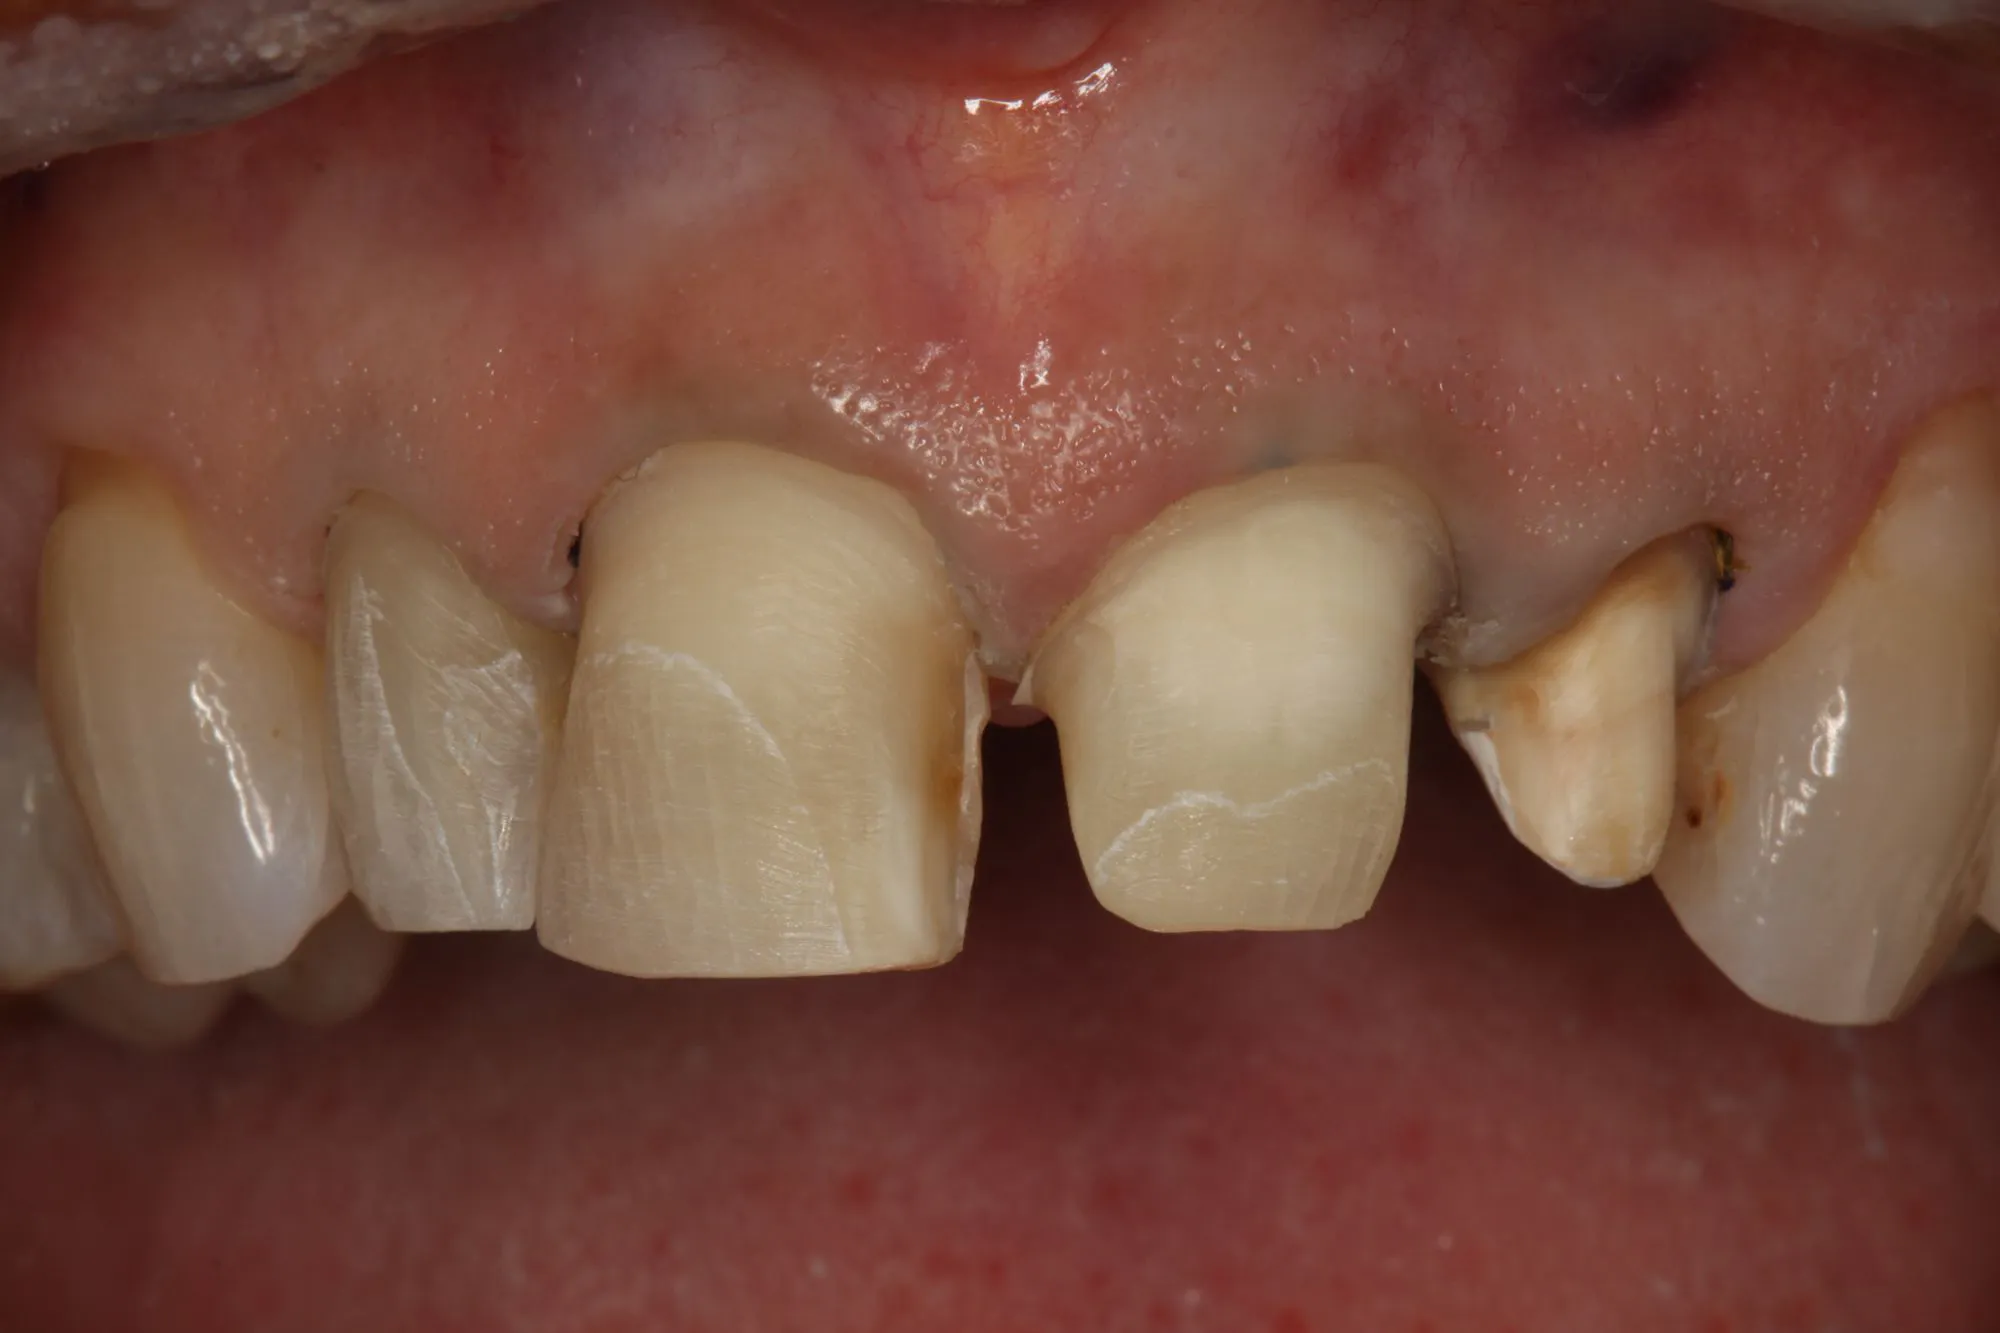

The CS 9600 features breakthrough innovations such as its artificial intelligence (AI)-powered positioning, video cameras, and Live Positioning Assistant to help enable users to produce high-quality images.

“The 5-in-1 CBCT scanner with extraordinary precision.”

Bringing dentists into the future of digital imaging